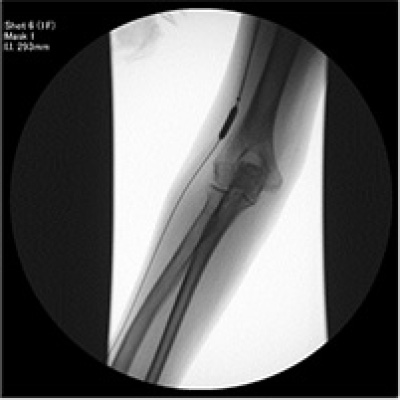

左の写真はPTA前の造影検査の写真です。黒く写っているのが、シャントになります。真ん中の写真では、狭い部分に対し、バルーン(風船)を膨らませて、血管を広げています。右の写真はPTA後の造影検査の写真です。